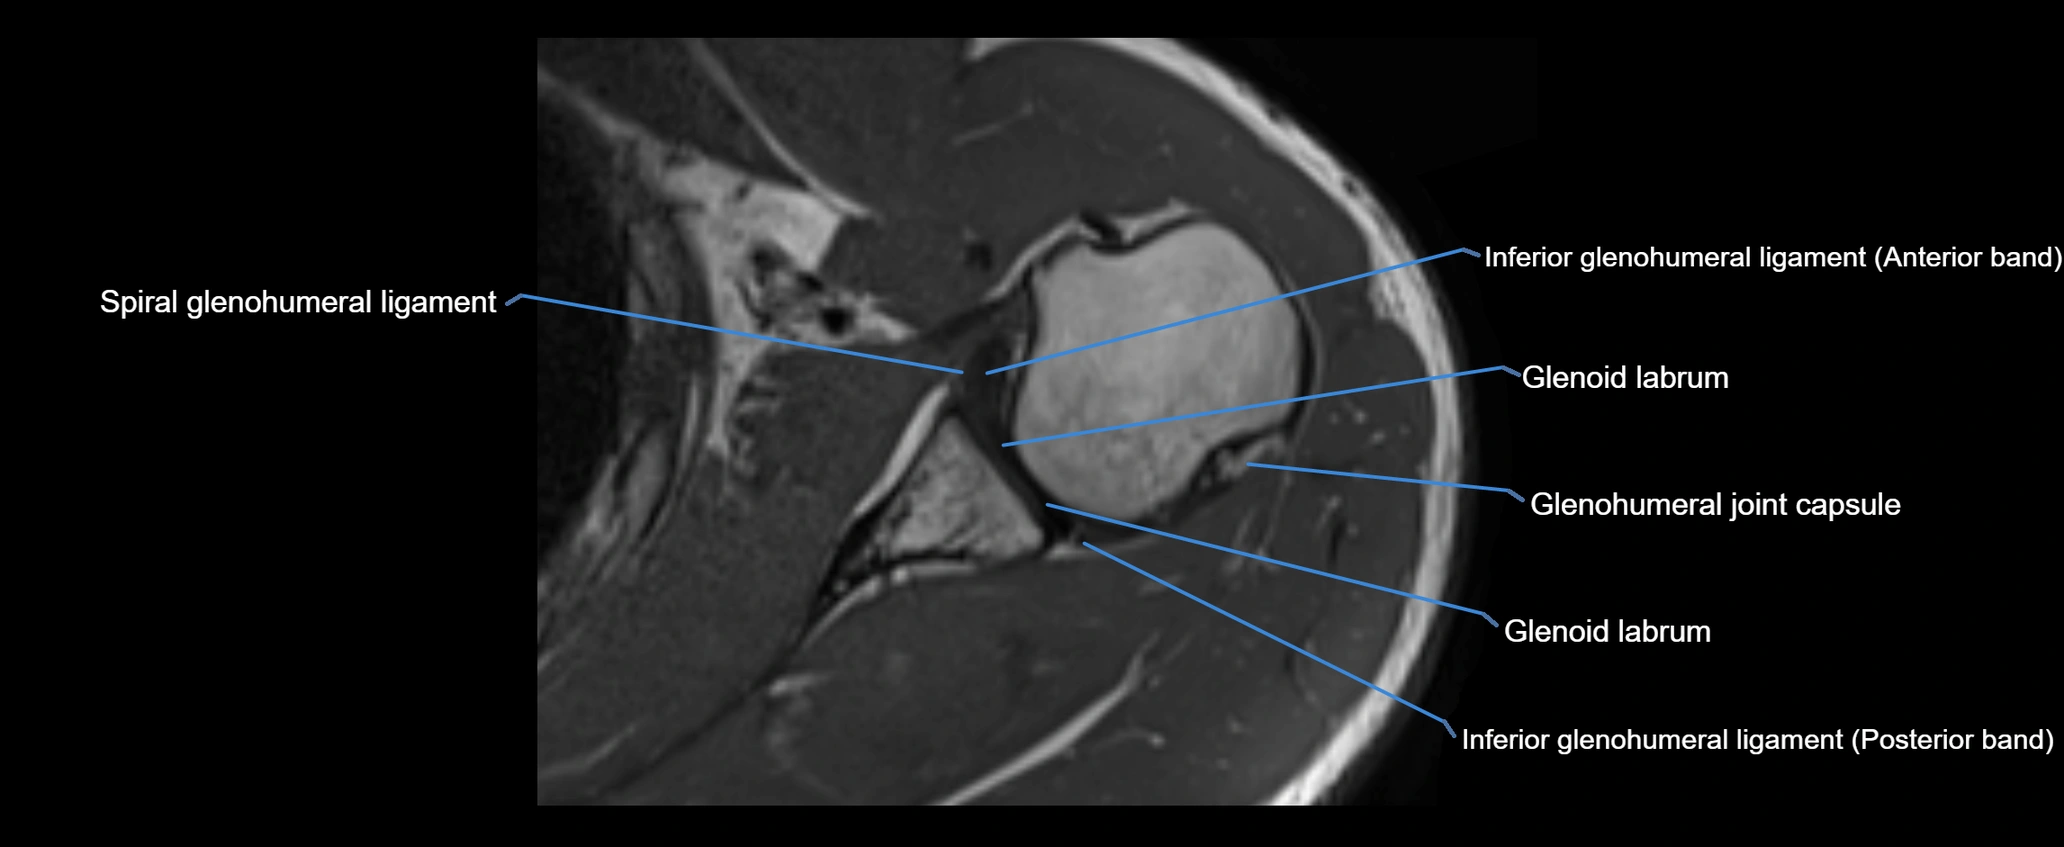

MRI images

image